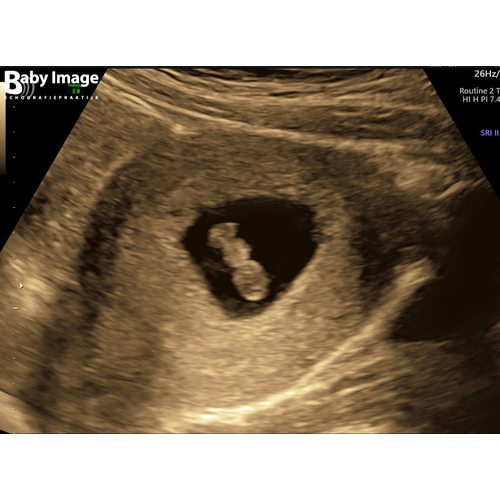

Als dit de volledige echo foto is die op beeld staat 鉂わ笍

Dan 馃挋馃挋馃挋馃挋馃挋